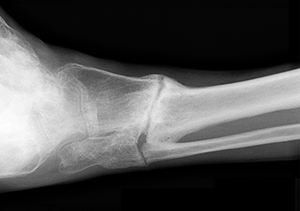

Non-union is the permanent failure of a bone to heal from a fracture. It occurs when the bone lacks adequate stability and support and/or blood flow to heal on its own without intervention. After a fracture occurs, new bone tissue forms to join the broken pieces. When the broken bone fails to heal permanently without intervention it is called a "Non-union". A fracture that is a minimum of nine months post occurrence and has not healed for three months is classified as a Non union.